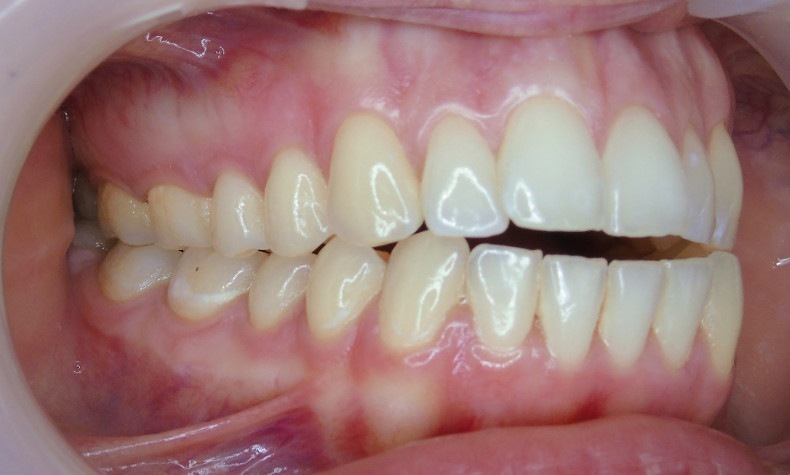

Der extraorale Befund (Abb. 1a–c) ergab ein gerades Durchschnittsgesicht mit leicht vergrößertem Nasolabialwinkel, ein symmetrisches Gesicht bei potenziell inkompetentem Lippenschluss sowie einen dolichofazialen Gesichtstyp. Intraoral lag beidseits annähernd eine Angle-Klasse I mit frontal offenem Biss (–2,5 mm) sowie ein dental-transversal zu schmaler Oberkiefer vor, woraus ein Kopfbiss von 13 und 23 resultierte. Des Weiteren zeigten sich ein persistierendes viszerales Schluckmuster und eine Inkongruenz der Kiefermitten (Abb. 2a–e; Abb. 3).

Durch sogenannte Optimized-Extrusion-Attachments wurde eine Extrusion der oberen Frontzähne von max. 2,3 mm und der unteren Frontzähne von max. 1,4 mm geplant (Abb. 4a–c). Mithilfe einer leichten Expansion der Prämolarenregion konnte der Platzmangel im Oberkiefer ohne ASR kompensiert werden.

Sechs Monate nach Abschluss der Therapie besteht weiterhin ein stabiles Ergebnis. Wie im Vergleichsbild (Abb. 5a–c) zu sehen ist, konnte die geplante vertikale Korrektur vollständig erzielt und die Mittellinie bis auf eine MLV von 1 mm nach rechts im UK korrigiert werden.